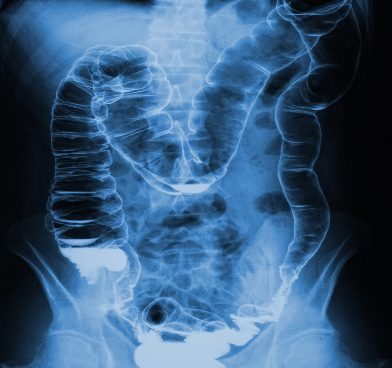

Naša crijeva su naš najveći organ. Kod odrasle osobe, crijeva su dugačka 8 metara, a površina im je oko 500 kvadratnih metara kada su raširena. To je gotovo veličina 2 teniska terena. Ogromna površina! Za usporedbu, pluća imaju površinu od 100 kvadratnih metara, a koža 2 kvadratna metra. Cjelokupna površina crijeva djeluje kao kontaktna točka s vanjskim svijetom. Hrana i piće se razgrađuju u crijevima i apsorbiraju preko crijevne sluznice. U crijevima se odlučuje od čega ćemo graditi svoje stanice i što će biti izlučeno. To je iznimno važan i vrlo složen zadatak. Sukladno tome, raznovrsni su poremećaji koji se mogu pojaviti na sluznici bolesnih crijeva. Vidite, bolesna crijeva mogu prouzročiti mnogo nevolja!

Naša crijeva su organ s najvećom površinom. Zbog toga su vrlo osjetljiva na patogene i upale. Oko 80% imunoloških stanica nalazi se u i oko crijeva. To je dobro jer se upravo tamo odlučuje hoćemo li se razboljeti ili ne. Ako crijeva nisu u redu, imunološki sustav je pod pritiskom. Može se razviti sklonost infekcijama ili alergijama.

Kada hrana stigne u crijeva, tek tada probava zapravo počinje. U tankom crijevu, gušterača luči sokove koji su važni za probavu ugljikohidrata i proteina. Jetra, putem žuči, doprinosi svojem dijelu kako bi masti bile pravilno razgrađene i apsorbirane. Kada se hrana razloži na male komponente, one se apsorbiraju kroz crijevnu sluznicu i tako dospijevaju u krvotok. Također, dijelovi žučnih sokova (npr. žučne kiseline) ponovno se apsorbiraju. Možemo reći, interno recikliranje.

U debelom crijevu postoje druge bakterijske kulture. One se, između ostalog, brinu da imamo dovoljno vitamina K. Osim toga, u debelom crijevu se apsorbira voda u tijelo.